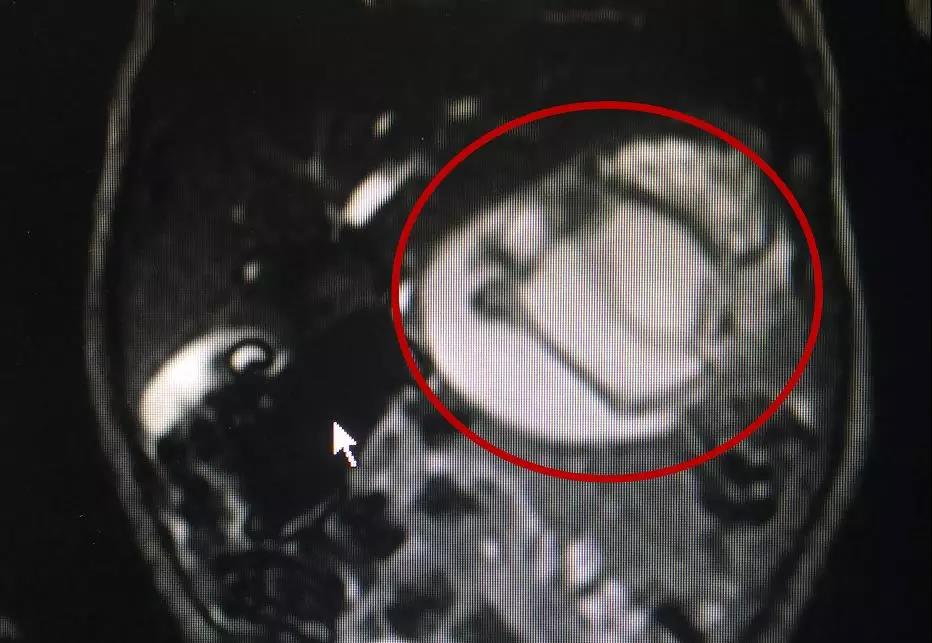

超聲檢查提示,她腹中胎兒的肚子里有一個包塊,醫(yī)生建議等孩子出生后到上級醫(yī)院做進(jìn)一步檢查。

“孩子出生以后就到我們醫(yī)院做了檢查,發(fā)現(xiàn)包塊里面有肢體有骨骼,考慮是一個寄生胎。”我院小兒外科副主任醫(yī)師夏順林說。

小兒外科李炳團(tuán)隊對冬冬進(jìn)行了會診,發(fā)現(xiàn)寄生胎位于胃和結(jié)腸后方中線偏左側(cè),緊靠著一個大血管,如果術(shù)中處理不好,很可能導(dǎo)致致命性的大出血。

這個寄生胎長約5厘米,已經(jīng)有了肢體的雛形。“大小相當(dāng)于一個發(fā)育到九周左右的胚胎,可以看出肢芽!

醫(yī)生從冬冬腹內(nèi)取出的寄生胎